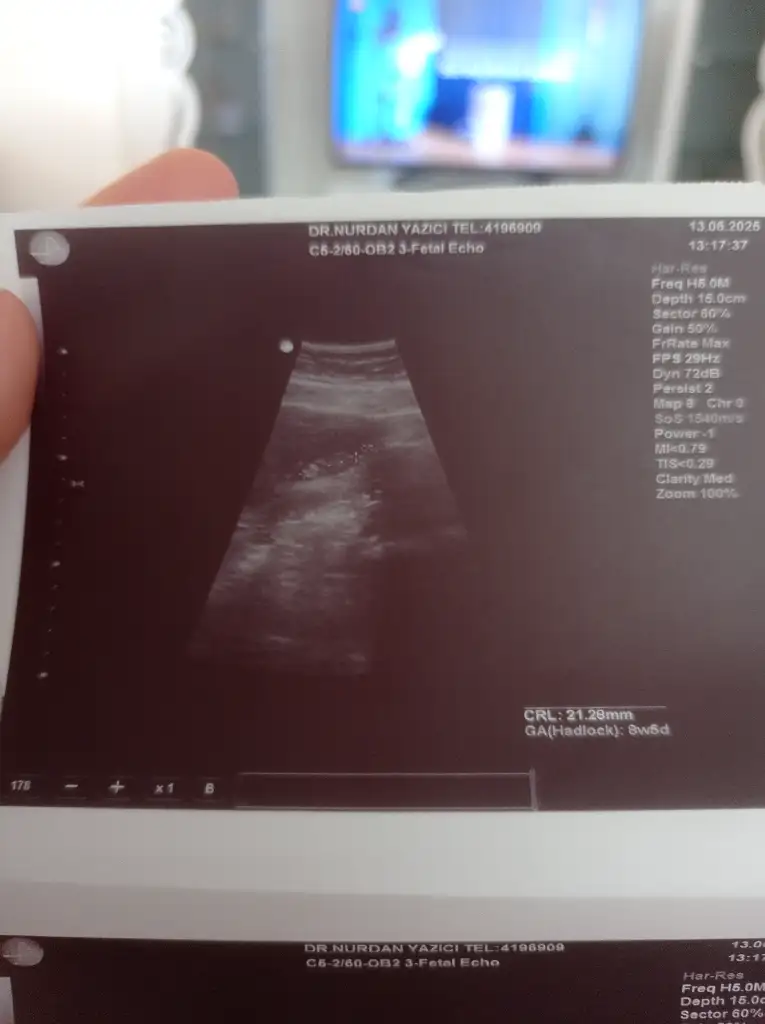

Doktor ilk erkek gibi sanki dedi ama sonrasında net değil dedi çıkıntı var ama erkek mi kız mı belli değil dedi. 3 hafta sonra artık

Erkek gibiKızlar 6 haftalık ultrason görüntüsü. Ultrasın görüntüsünden cinsiyet tahmini yapanlar varmış. Bi bakabilir misiniz rica etsem

Bariz kız görüyorum, hayırlısıyla sağlıcakla gelsin inşallahArkadaşlar benimde ultrason goruntume bakar mısınız 13+4 haftalık cinsiyeti nedir sizce